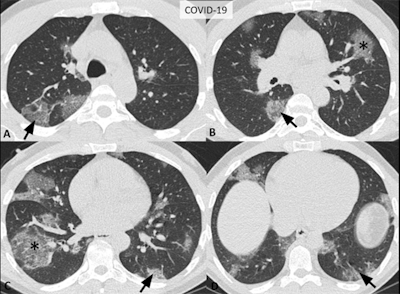

Images of a 52-year-old man confirmed to have COVID-19 showing typical CT features, including bilateral, multifocal rounded ground-glass opacity (asterisks) and peripheral ground-glass opacity (arrows) with superimposed interlobular septal thickening and crazy-paving pattern (i.e., visible intralobular lines). Image courtesy of the RSNA.Structured reporting in the setting of COVID-19 could help address some of these issues and increase efficiency in medical care during the ongoing pandemic, Litt and colleagues noted. A standardized reporting system for COVID-19 findings on CT could result in other benefits as well, including the following:

- Typical appearance: Commonly reported CT findings of greater specificity for COVID-19 pneumonia, including peripheral, bilateral ground-glass opacity, and crazy-paving pattern. Principal differential diagnoses include viral pneumonias, especially influenza, and acute lung injury patterns such as organizing pneumonia.